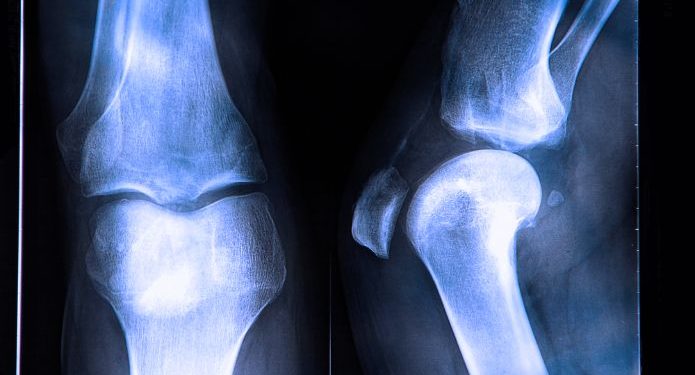

Surgery is the main treatment for bone cancer. For most types of bone cancer, the surgeon will remove the tumor and a small amount of healthy tissue around it. This type of surgery is called wide excision surgery. The surgeon will use special techniques to make sure that all the cancer is removed. If the limb (arm or leg) affected by the tumor is still functional, surgeons may be able to perform limb-sparing surgery. The lost limb will be replaced with a metal prosthesis or with bone from another part of the body or a bone bank.